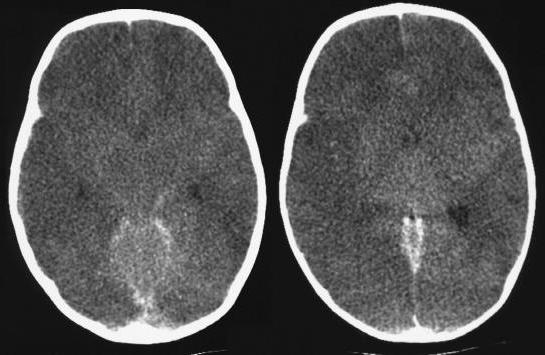

- магнитно-резонансная или компьютерная томография помогают определить размеры, распространение и место расположения отека и, соответственно, оценить состояние пациента и риск для его жизни;